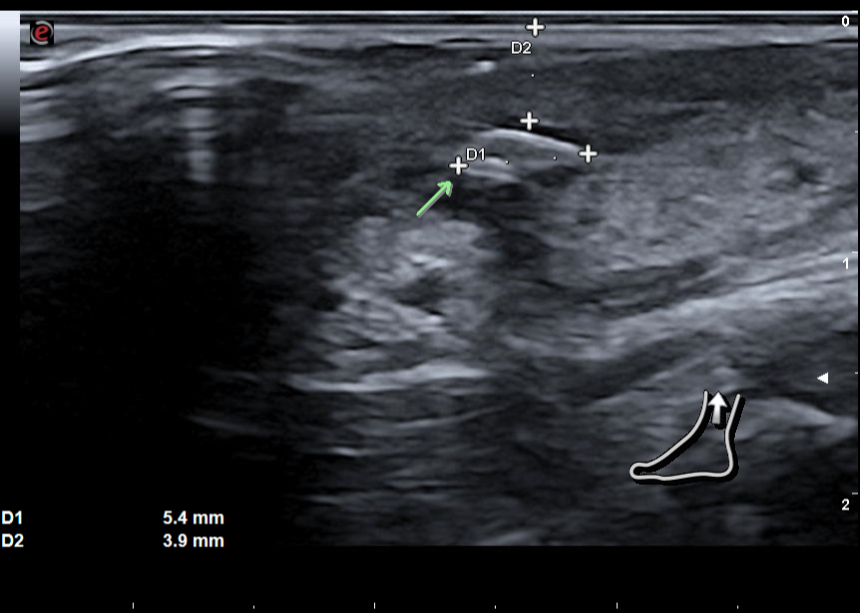

Decido realizar ecografía en cara lateral del tobillo izquierdo.

Hallazgos ecográficos

En la ecografía con sonda lineal, se aprecia material hiperecogénico de 5 mm en diámetro longitudinal en tejido subcutáneo, sin sombra acústica, con reborde anecogénico, a 4 mm de superficie de piel y signos de empedrado en tejido subutáneo. Compatible con cuerpo extraño en tejido subcutáneo con celulitis asociada.